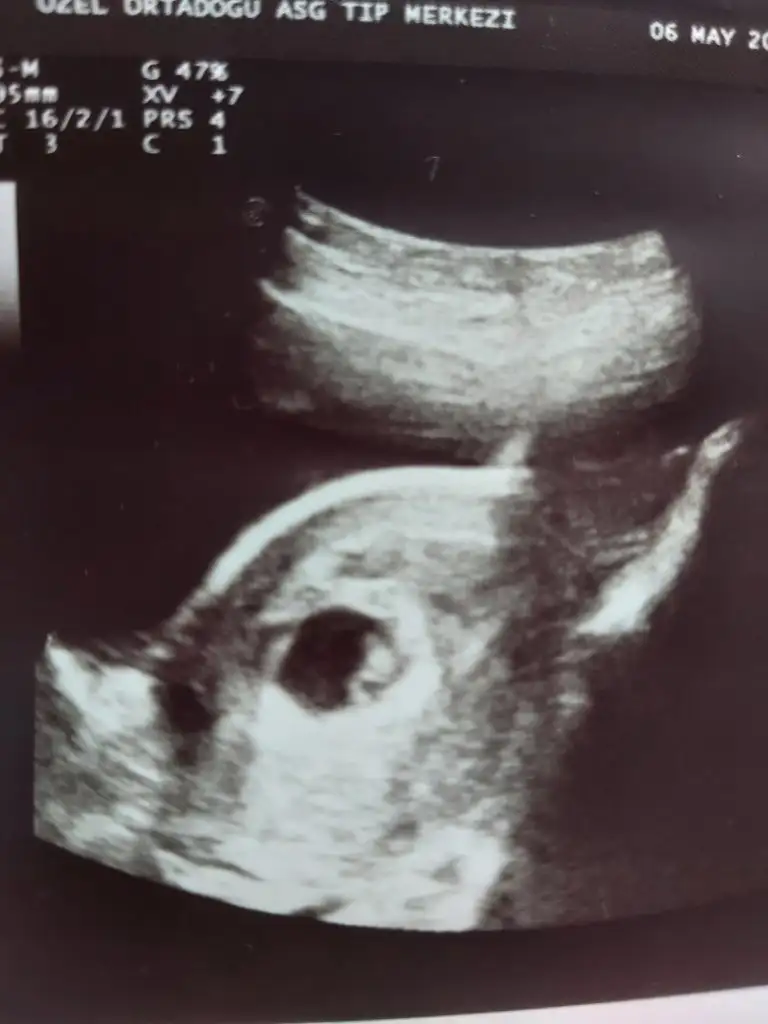

Burda 6+2 karnından ultrason fotosu 2. Gebelik cinsiyet tahmini yapabilirmisiniz

2. Gebeligim 3 yaşında dünyalar tatlısı bir kızım varerkek gibi canım, ilk bebeğin ne oldu